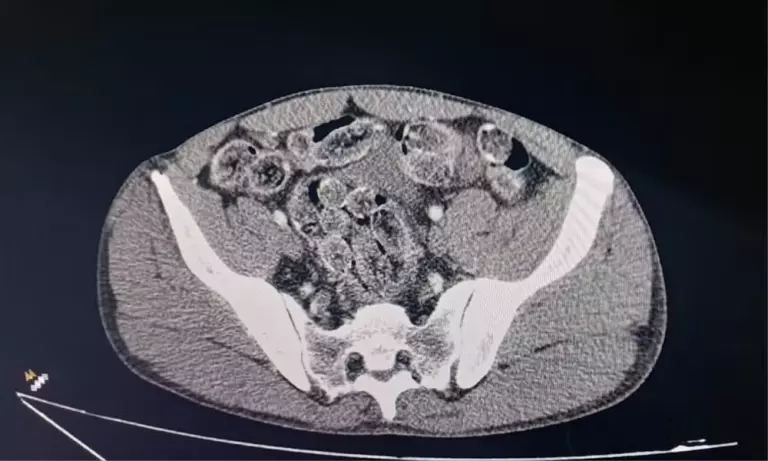

Os dois homens confessaram ainda ter ingerido parte da droga. Eles foram encaminhados ao Conjunto Hospitalar de Sorocaba (CHS), onde exames constataram a presença de cápsulas no estômago.